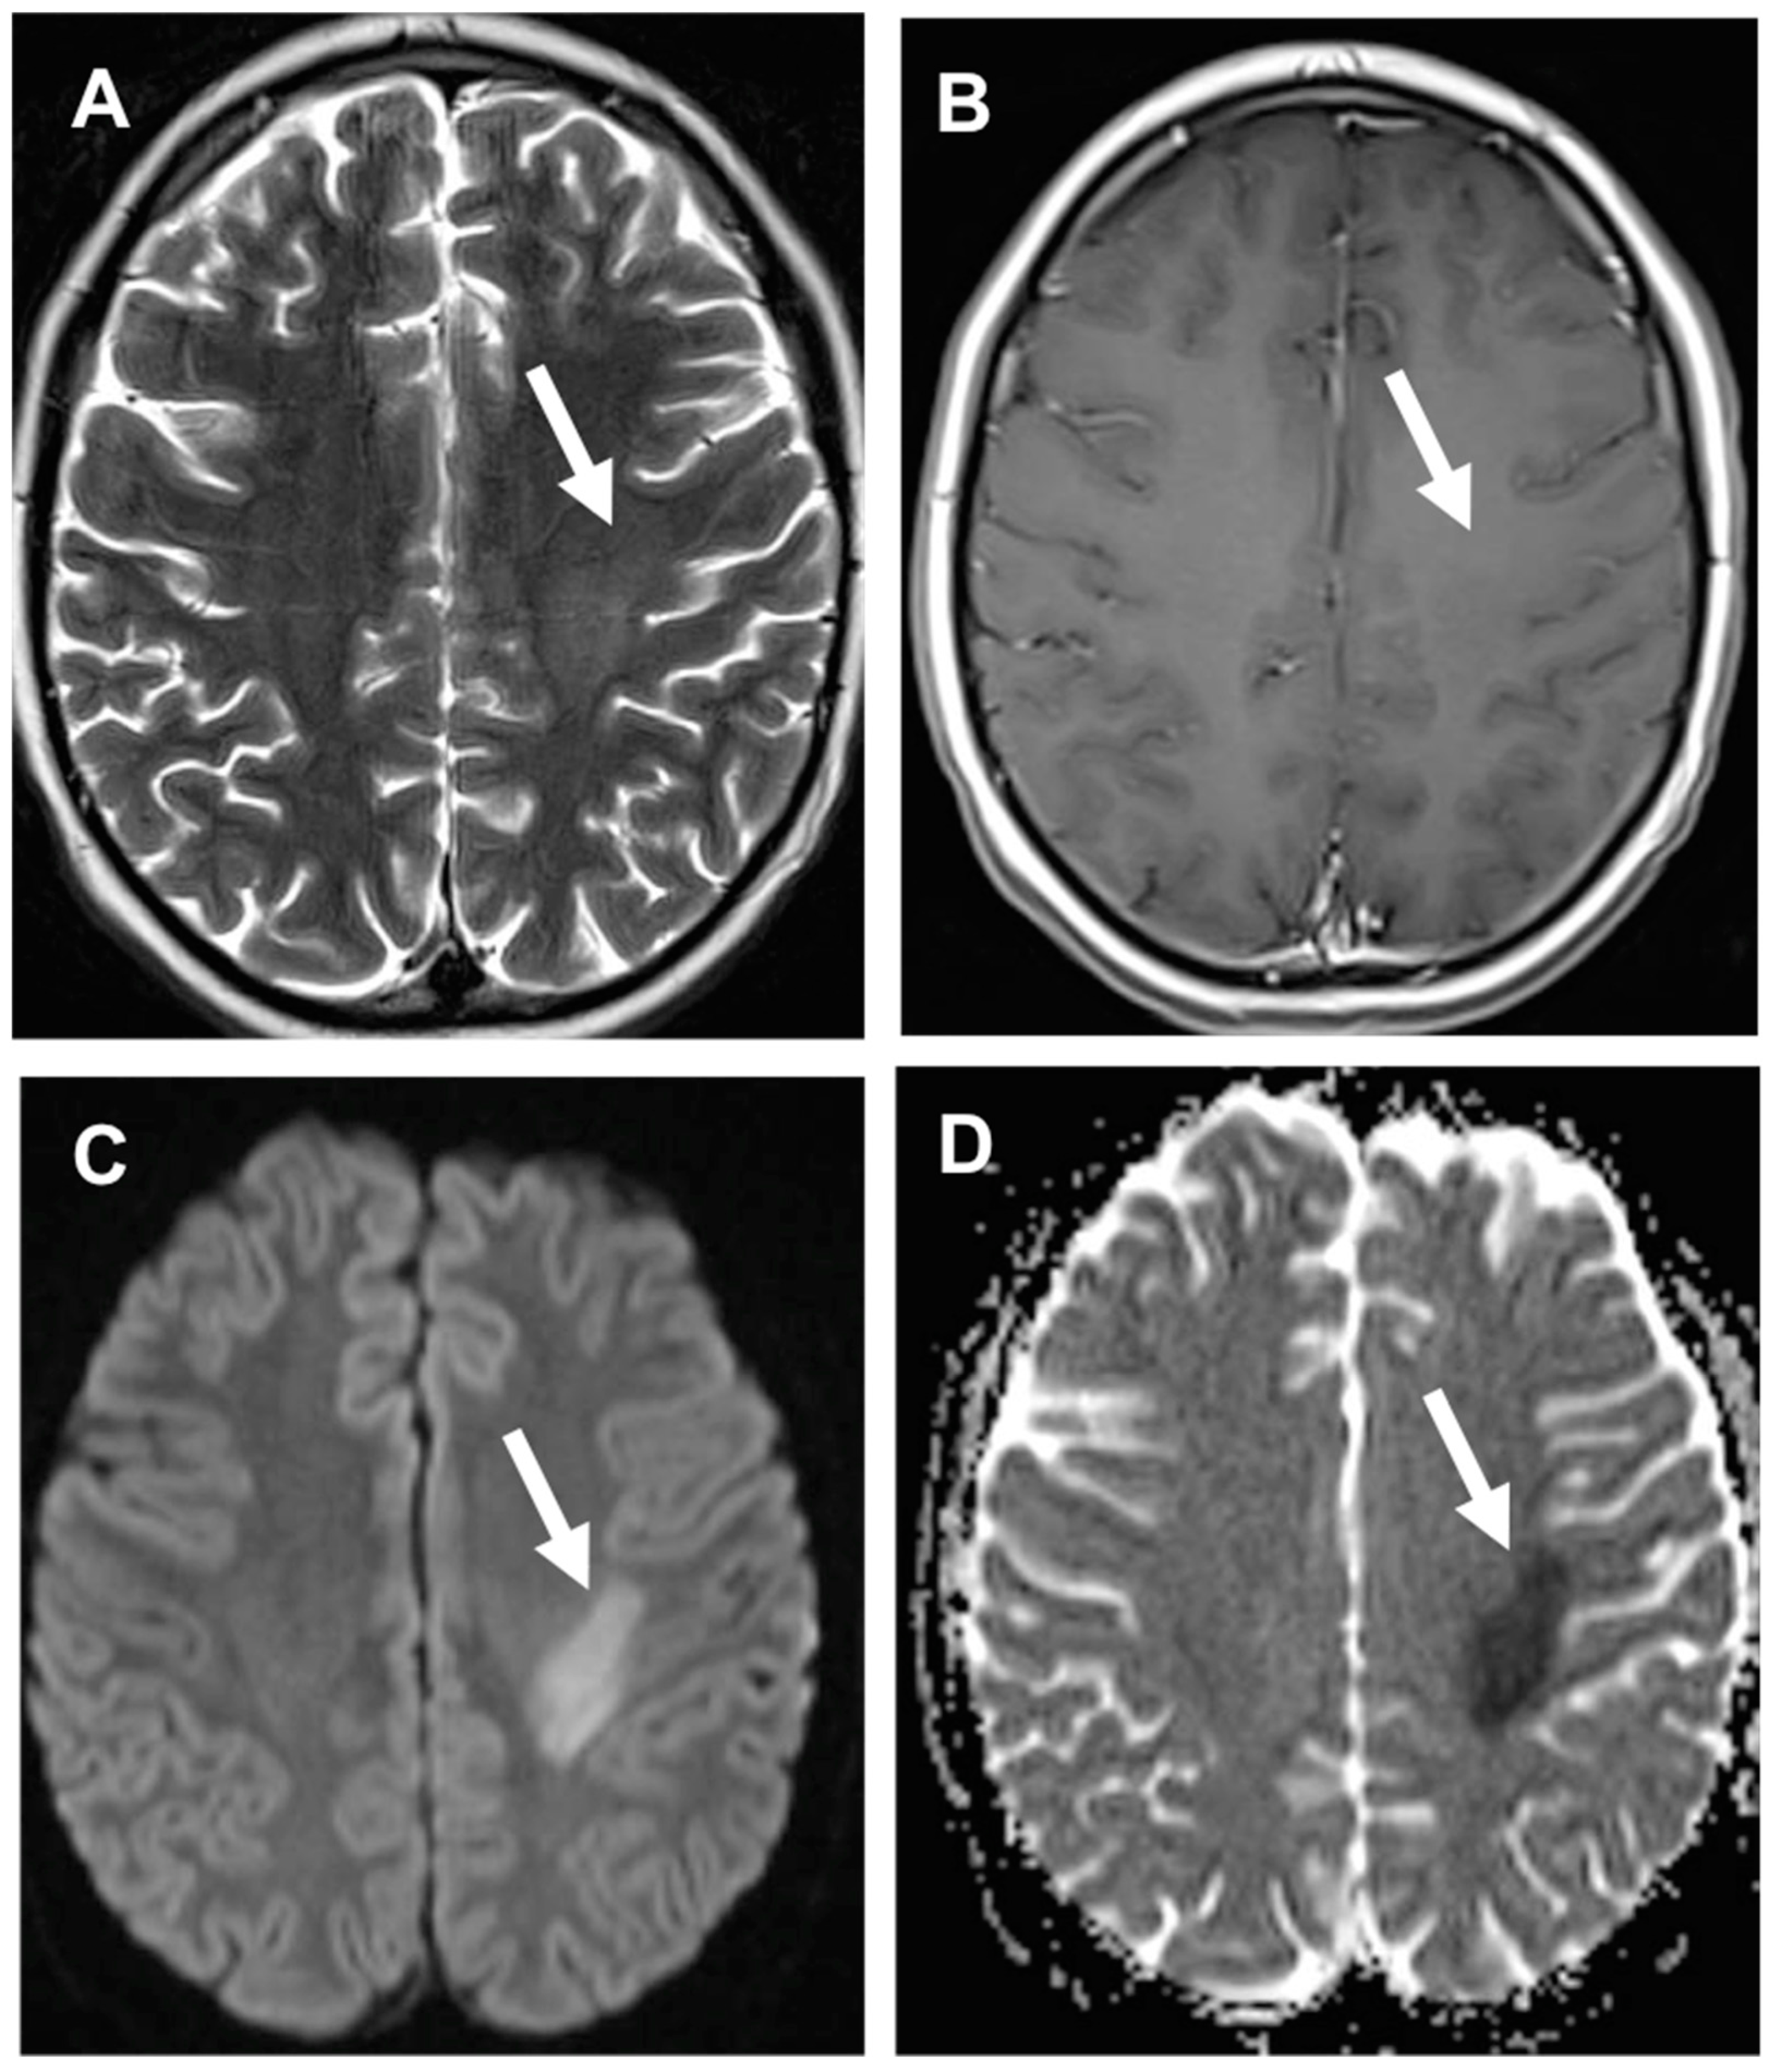

3.3. Stroke-like Migraine Attacks after Radiation Therapy

- Kerklaan, J.P.; Lycklama á Nijeholt, G.J.; Wiggenraad, R.G.J.; Berghuis, B.; Postma, T.J.; Taphoorn, M.J.B. SMART syndrome: A late reversible complication after radiation therapy for brain tumours. J. Neurol. 2011, 258, 1098–1104. [Google Scholar] [CrossRef] [PubMed] [Green Version]

- Rigamonti, A.; Lauria, G.; Mantero, V.; Filizzolo, M.; Salmaggi, A. SMART (stroke-like migraine attack after radiation therapy) syndrome: A case report with review of the literature. Neurol. Sci. 2016, 37, 157–161. [Google Scholar] [CrossRef]

- Armstrong, A.E.; Gillan, E.; Di Mario, F.J. SMART Syndrome (Stroke-Like Migraine Attacks After Radiation Therapy) in Adult and Pediatric Patients. J. Child Neurol. 2014, 29, 336–341. [Google Scholar] [CrossRef]

- Farid, K.; Meissner, W.G.; Samier-Foubert, A.; Barret, O.; Menegon, P.; Rouanet, F.; Fernandez, P.; Orgogozo, J.M.; Allard, M.; Tison, F.; et al. Normal Cerebrovascular Reactivity in Stroke-Like Migraine Attacks After Radiation Therapy Syndrome. Clin. Nucl. Med. 2010, 35, 583–585. [Google Scholar] [CrossRef]

- Black, D.F.; Morris, J.M.; Lindell, E.P.; Krecke, K.N.; Worrell, G.A.; Bartleson, J.D.; Lachance, D.H. Stroke-Like Migraine Attacks after Radiation Therapy (SMART) Syndrome Is Not Always Completely Reversible: A Case Series. Am. J. Neuroradiol. 2013, 34, 2298–2303. [Google Scholar] [CrossRef] [Green Version]

- Ito, H.; Mori, K.; Kagami, S. Neuroimaging of stroke-like episodes in MELAS. Brain Dev. 2011, 33, 283–288. [Google Scholar] [CrossRef] [PubMed]